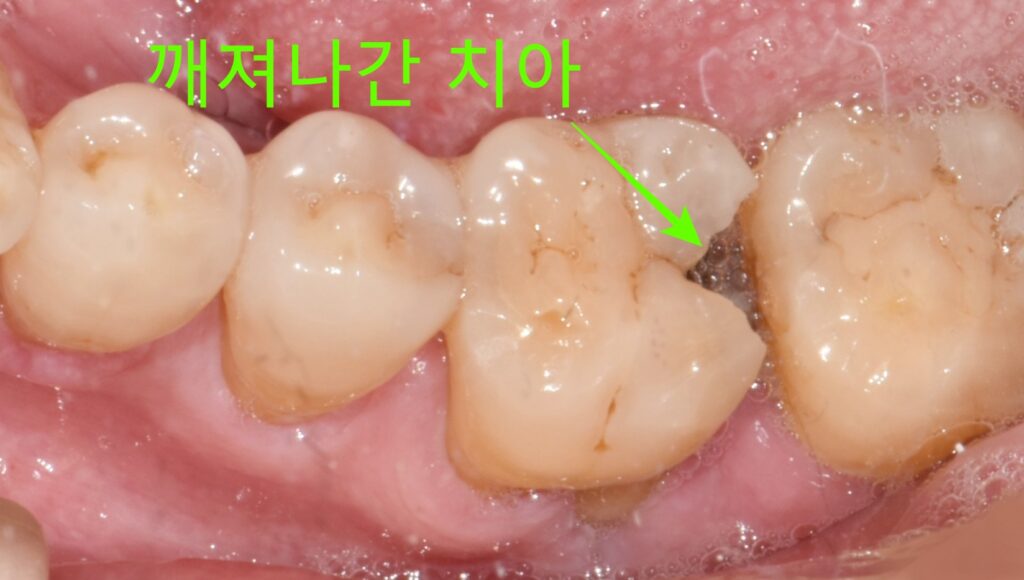

내원하신 환자분은 어금니에 심한 충치(우식)가 있는 상태였습니다.

- 주소(Chief Complaint): 어금니 통증 및 불편감

- 타 치과 진단: 우식이 너무 깊어 발치 권유

- 내원 이유: 치아를 최대한 살리는 치료를 받고 싶어서

X-ray와 임상 검사 결과, 우식의 깊이가 실제로 상당했습니다. 신경(치수)에 근접하거나 이미 영향을 미쳤을 가능성이 높은 상태로, 치아를 살리는 것이 쉽지 않아 보였습니다. 그러나 발치 전, 할 수 있는 모든 시도를 해보기로 했습니다.